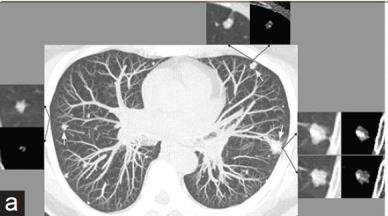

女性,61岁,无吸烟史。

肺CT平扫显示多个双侧分叶状大小不等的肺结节,许多伴有粗大的钙化。最大的结节在左上叶约14 mm,与之前的CT相比,无增大。

PET-CT显示肺结节对氟脱氧葡萄糖 (FDG) 的摄取极少。

诊断结果:上皮样血管内皮瘤(中低级别血管恶性肿瘤)